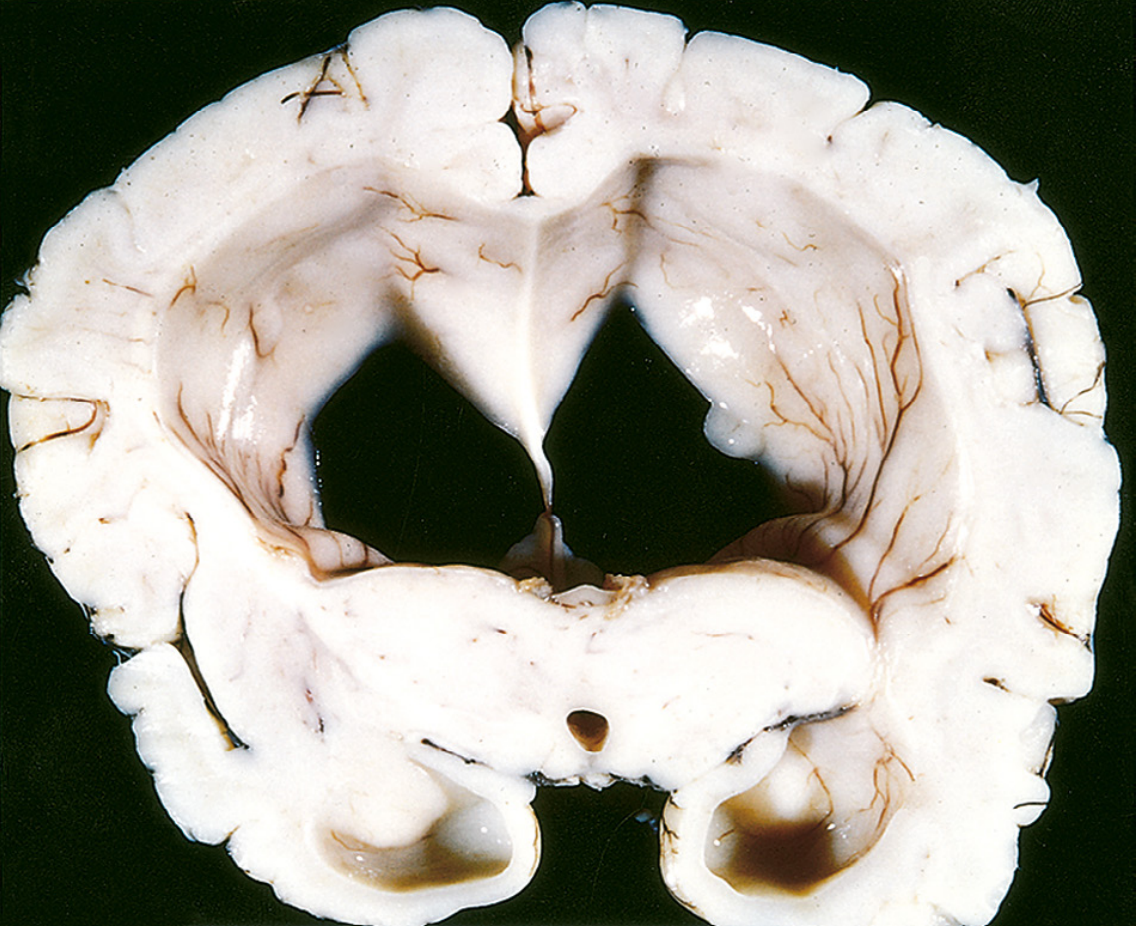

Hydrocephalus — dilated lateral ventricles in coronal section (Robbins & Kumar)

Dilated lateral ventricles in a brain with atrophy (hydrocephalus ex vacuo), coronal section — Robbins, Cotran & Kumar

Ventriculomegaly secondary to cerebral atrophy is formally termed hydrocephalus ex vacuo. It is a compensatory, passive enlargement of the ventricular system (and subarachnoid spaces) that occurs when the brain loses parenchymal volume. As neurons and white matter are lost, CSF fills the resulting "empty" space — but this is NOT true hydrocephalus (intracranial pressure is normal or low, not elevated).

"Hydrocephalus ex vacuo is simply a descriptive term and is not itself responsible for any pathology. It refers to excess CSF in a region where brain tissue was lost as a result of stroke, surgery, atrophy, trauma, or other insult." — Neuroanatomy through Clinical Cases, 3rd Edition